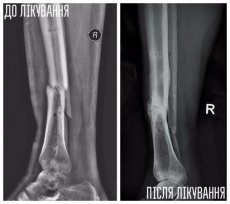

Юрій — боєць 51 ОМБр, травму отримав у липні 2014 року під Слов'янськом. Авто, яким кермував Юрій, підірвалося на ворожому фугасі, осколками тяжко травмувало руку і ногу хлопця. Юрія лікували у трьох шпиталях, та навіть за рік зусиль лікарів кістки гомілки не зрослися.У місці перелому почав формуватися несправжній суглоб, ногу тяжко викрутило — хлопець ледве пересувався навіть на милицях.